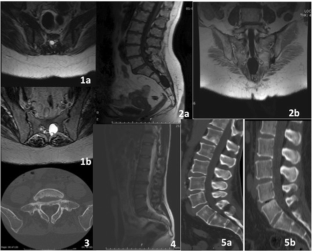

Fig. 1